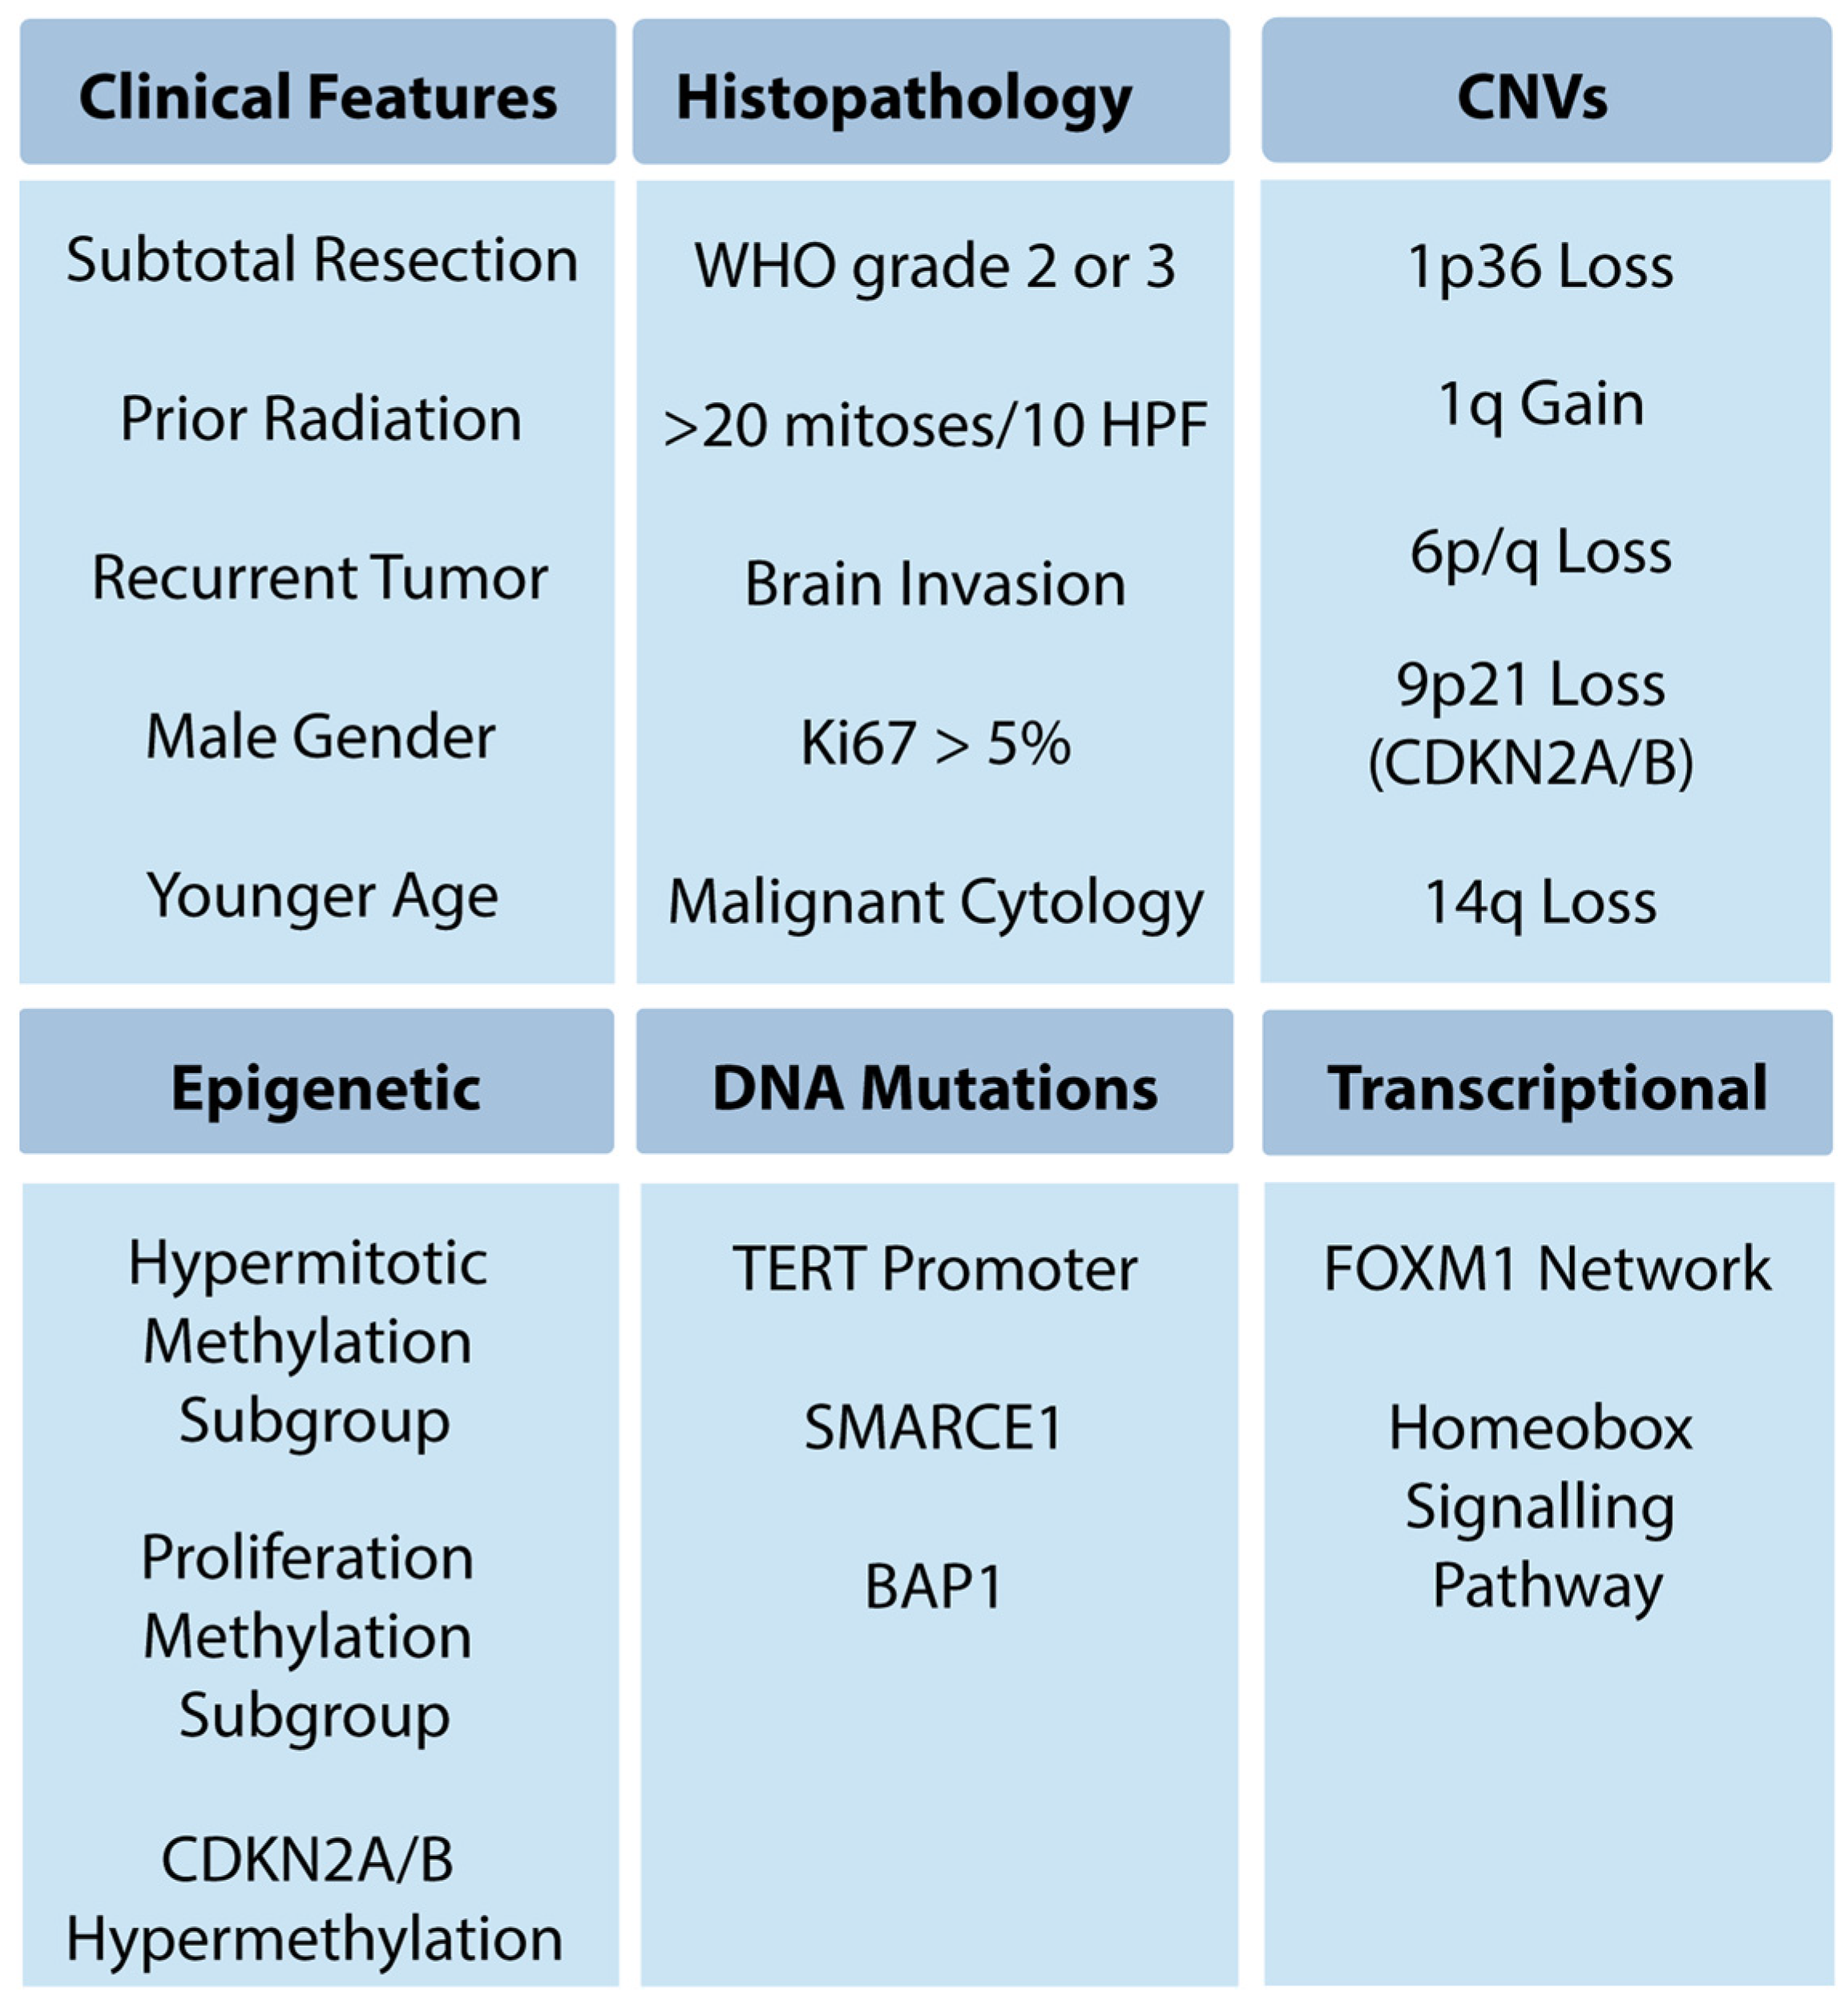

Typical Meningioma | Cohen Collection | Volumes | The。The Evolving Classification of Meningiomas: Integration of。Predicting Histologic Grade of Meningiomas Using a Combined。Meningiomas, Part II (Volume 170) (Handbook of Clinical Neurology, Volume 170) ハードカバー – 2020/8/14英語版 Michael W. McDermott MD (編集)※中古品のため、使用できれば良いという方のみのご購入をお待ちしております。角に少々イタミあり。中古品のため、多少のスレ、イタミ等ありますが、書き込みなく、とても良好な状態です。※商品状態の少々の見落としはご理解下さい。※値引交渉にはお答え致しません。※希少品の為、定価より高額の場合があります。※都合により発送方法を変更する場合があります。【佐川急便/日本郵便から佐川急便/日本郵便及びその逆等】※ビニールにて梱包し発送致しますが、保管、輸送によるイタミ等はご容赦下さい。※コメント不要、即購入にてご注文お願いします。。EANO guidelines for the diagnosis and treatment of。野口晴哉 口述 整体操法初等講座 全25冊。健康・医学専門雑誌コレクション。QB RB 2冊セット おまけ付き 看護師国家試験 2025年114回。【新品未使用】イヤーノート2026、内科専門医•総合内科専門医セット【バラ売可】。★8割復元!2024年度JBPOT復元。望診 自然療法 代替療法 医療 看護 大森英桜 日本CI協会 マクロビオティック。【裁断済み】メカニカル・リンク : オステオパシー・アプローチ。橋本